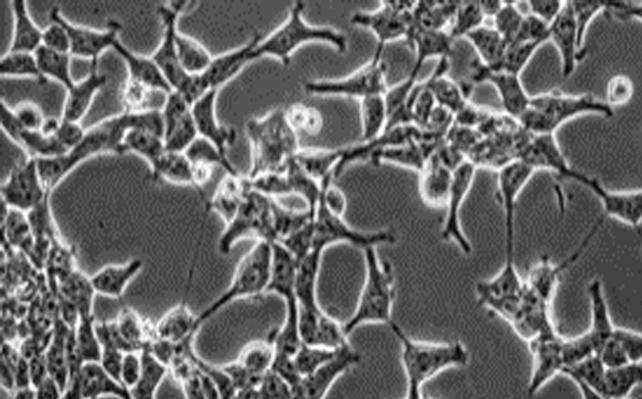

FTC-133;人甲状腺癌细胞